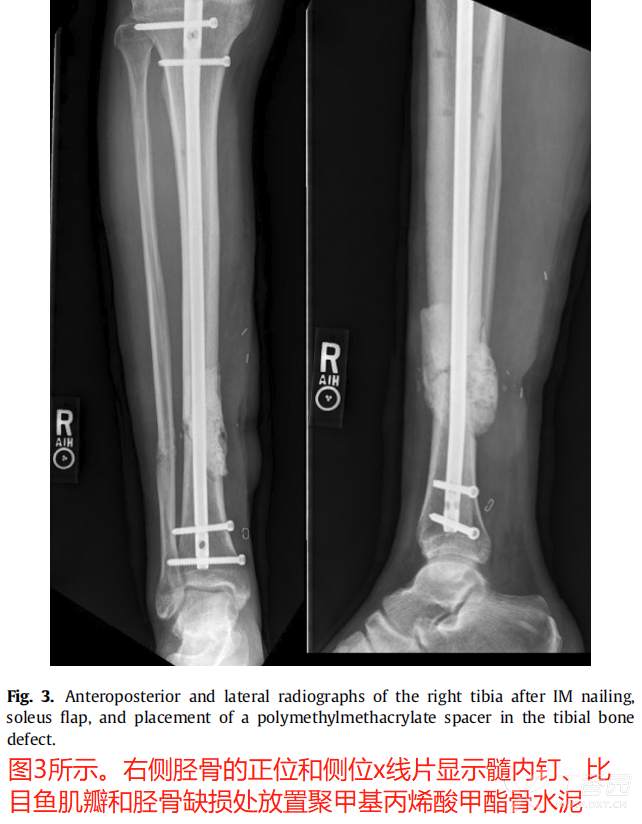

典型病例: